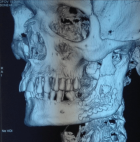

Sagittal split osteotomy (SSO) of the mandible is still an important part of orthognathic surgery, but “bad split” fractures that happen during the surgery are still a big problem. This report describes a rare case of bilateral bad split associated with highly compact mandibular bone (D1–D2 type) in a 53-year-old male undergoing mandibular advancement. The bone was too hard for the piezoelectric and rotary tools to work, and there was very little bleeding. This caused fractures in the cortex and lingual. Postoperative computed tomography confirmed the presence of highly dense bone, correlated with delayed healing and recurrence. Consistent pre-surgical CT scanning for an assessment of the density of the mandibular bone can provide essential information about the potential risk of the osteotomy procedure in the patient. Performing a careful bone quality and density examination pre-operatively will allow the surgeons to select the most appropriate instruments and surgical techniques that will fit the patient’s individual anatomy. Such a point escalates to being very significant when dealing with the geriatric population, as bone density increase can not only alter the fracture behavior but also the recovery process during and after surgery. The inclusion of regular CT-based bone density evaluations into the preoperative routine not only facilitates the anticipation of surgical difficulties but also results in safer and more efficient osteotomies.

Figure 1